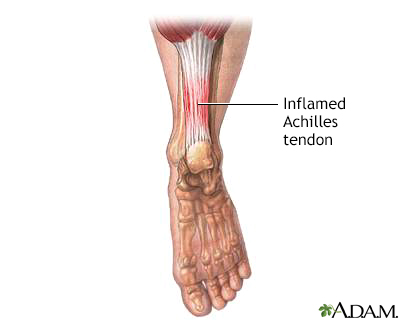

Achilles tendinitis Information Mount Sinai New York

Causes of Achilles Tendon Pain Advanced Foot Ankle Care

Achilles tendonitis pain causes symptoms and exercises

Achilles tendon pain Causes. when to see a doctor and treatment